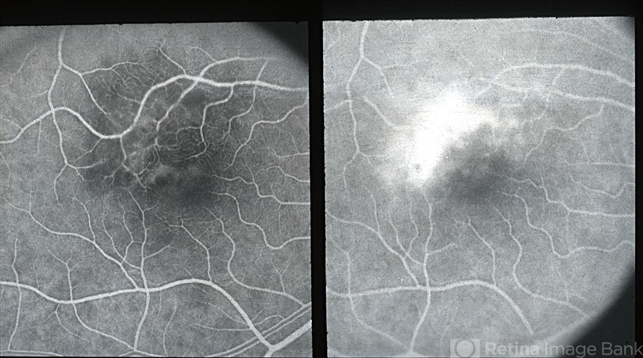

- macular edema, microangiopathy, retinal necrosis

- early and late phase FA showing paramacular nonperfusion and capillary dilatation with late leakage; presumably from herpes-associated retinal necrosis